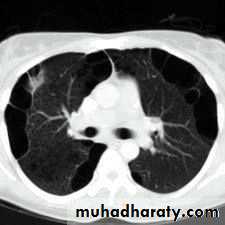

CT scan

BronchoscopyPneumothorax

Emphysema